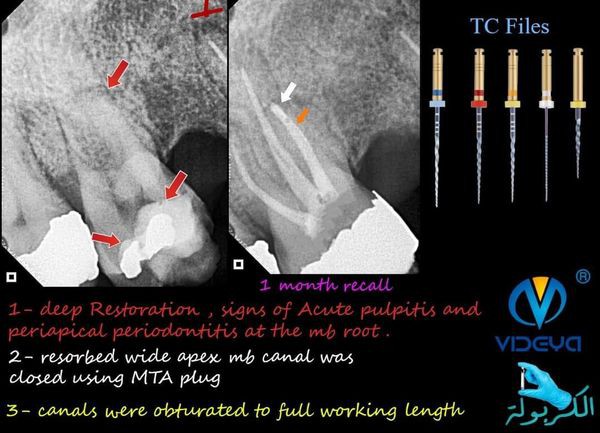

it was just a routine endodontic treatment for first upper molar with acute pulpitis till my apex locator which i trust went mad in the mesiobuccal canal.

all canals length were on average but MB canal was about 16 mm which is very abnormal and goes against my preoperative radiograph.

on A CBCT view the mb canal had a periapical lesion that caused a pathologically resorbed wide open apex with leakage of large amount of fluid into the canal.

the canal was retreated till the full working length and after 3 visits we managed to get a dry canal,apical 3rd was closed using MTA & MTA Carier .6 (angelus).

then obturation material was set to the remaining canal space,case reported a post operative moderate pain that lasted for 24 hour,after 1 month follow up the case was a symptomatic and pain free.